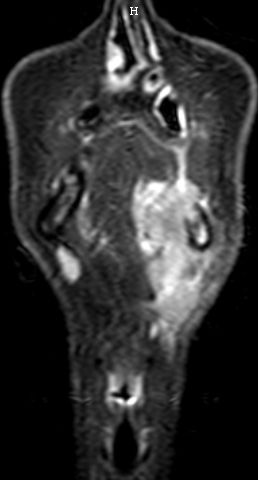

| MRT | Mundbodenkarzinom rechts T4 N2b Mo![]() ![]() ![]() |